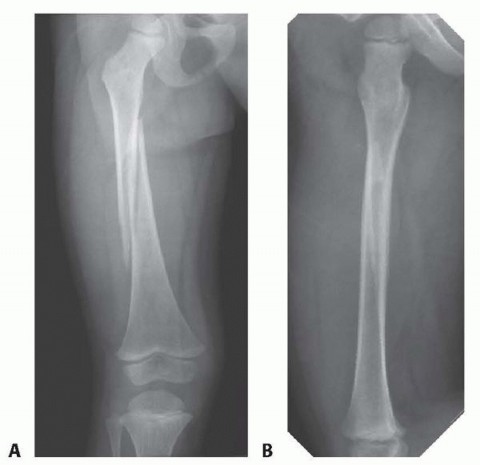

Chapter 30 Pediatric Tibial Fractures Craig P. Eberson DEFINITION Fractures of the tibia are common in childr…